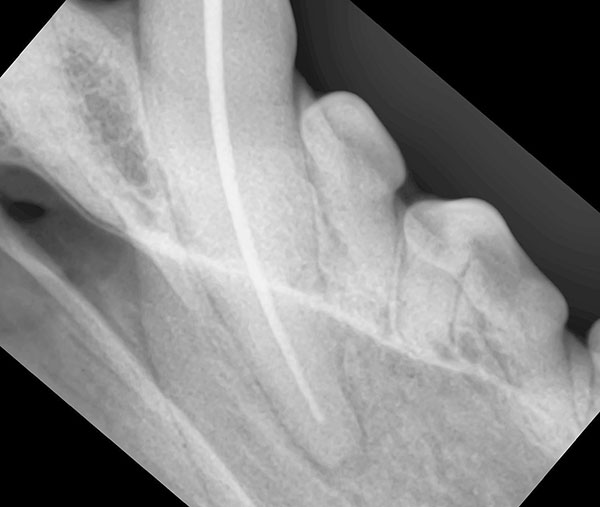

左第4前臼歯平板破折

ファイルによる抜髄

根管充填

歯冠修復

髄腔穿孔

根管口明示 作業長決定